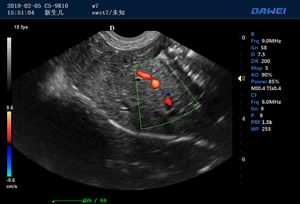

·支持B、C、PW、CW、寬景成像

·適用于各種動物的臨床腹部、胸腔,心臟、肌腱、小器官、眼球、生殖系統等的檢查